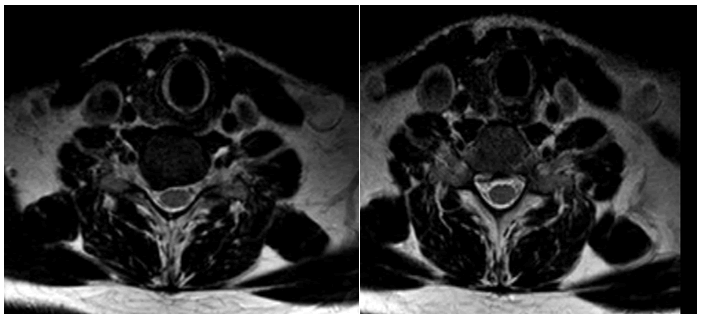

Journal-Neurological-Disorders-MRI

Figure 1. MRI lumbar spine T2 sagittal and axial view of a female patient has lower back pain and left sciatic pain shows: L5/S1 level left mediolateral disc protrusion, indenting the thecal sac and severely compromising the left exiting neural foramina.

Journal-Neurological-Disorders-Lumbar

Figure 2. MRI lumbar spine T2 sagittal and axial view of the same patient after one year with conservative treatment shows reduction of both L4- and L5 disc prolapse.